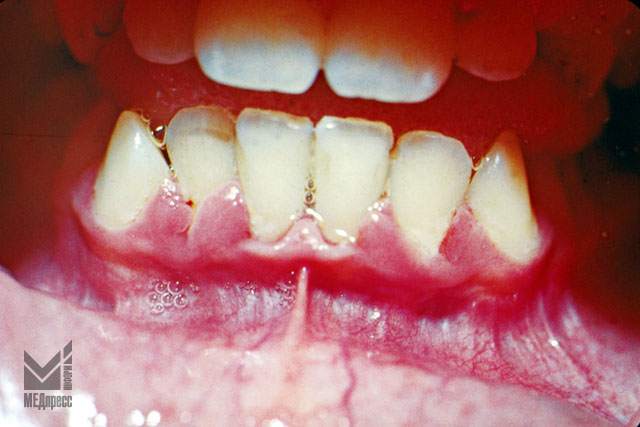

Рис. 7.Открытый прикус. Деформация челюстей и десневого края. Застойная гиперемия, отек. Оголение шеек центральных резцов, зубной камень.